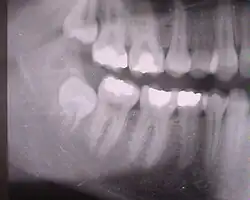

Die folgenden Röntgenbilder sind Ausschnitte aus Orthopantomogrammen (OPG):

Weisheitszahn 38; retiniert und verlagert – stark nach mesial gekippt; sehr kurze Wurzelspitzen projizieren sich auf den Nervus alveolaris inferior